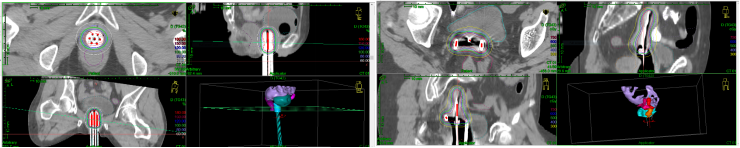

治疗中施源器植入过程顺利,患者耐受性良好,团队通过CT扫描进行定位,精确勾画HR-CTV与周围危及器官,利用TPS优化放射源驻留位置与时间,精细调整剂量分布,在确保靶区获得足够治疗剂量的同时,最大程度地降低了周围正常组织的受照剂量。治疗过程顺利,效果良好。